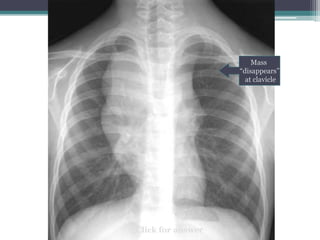

Which compartment do you think this mass is in?

Click for answer

Mass

โ€œdisappearsโ€

at clavicle

Cervicothoracic sign

โ€ข Answer: Mass lies in anterior mediastinum. We

know this because it disappears at the level of the

clavicle where it extends into the neck.

โ€ข This particular example is Non-Hodgkins lymphoma